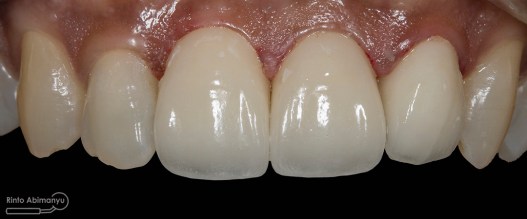

Begini hasil akhir setelah sementasi crown…

Alhamdulillah pasien nya senang sekali…. dia puas dan saya pun senang karena dapat memenuhi keinginan pasien…..

Nah ini resume foto before dan after perawatannya…